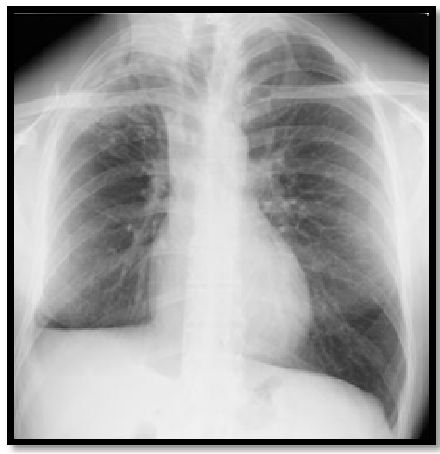

图10:胸部X线片显示右上叶的气囊实变区域。

abp在医学是什么意思如何区分4种类型的肺曲霉菌病影像学表现?_https://www.jmylbn.com_新闻资讯_第13张